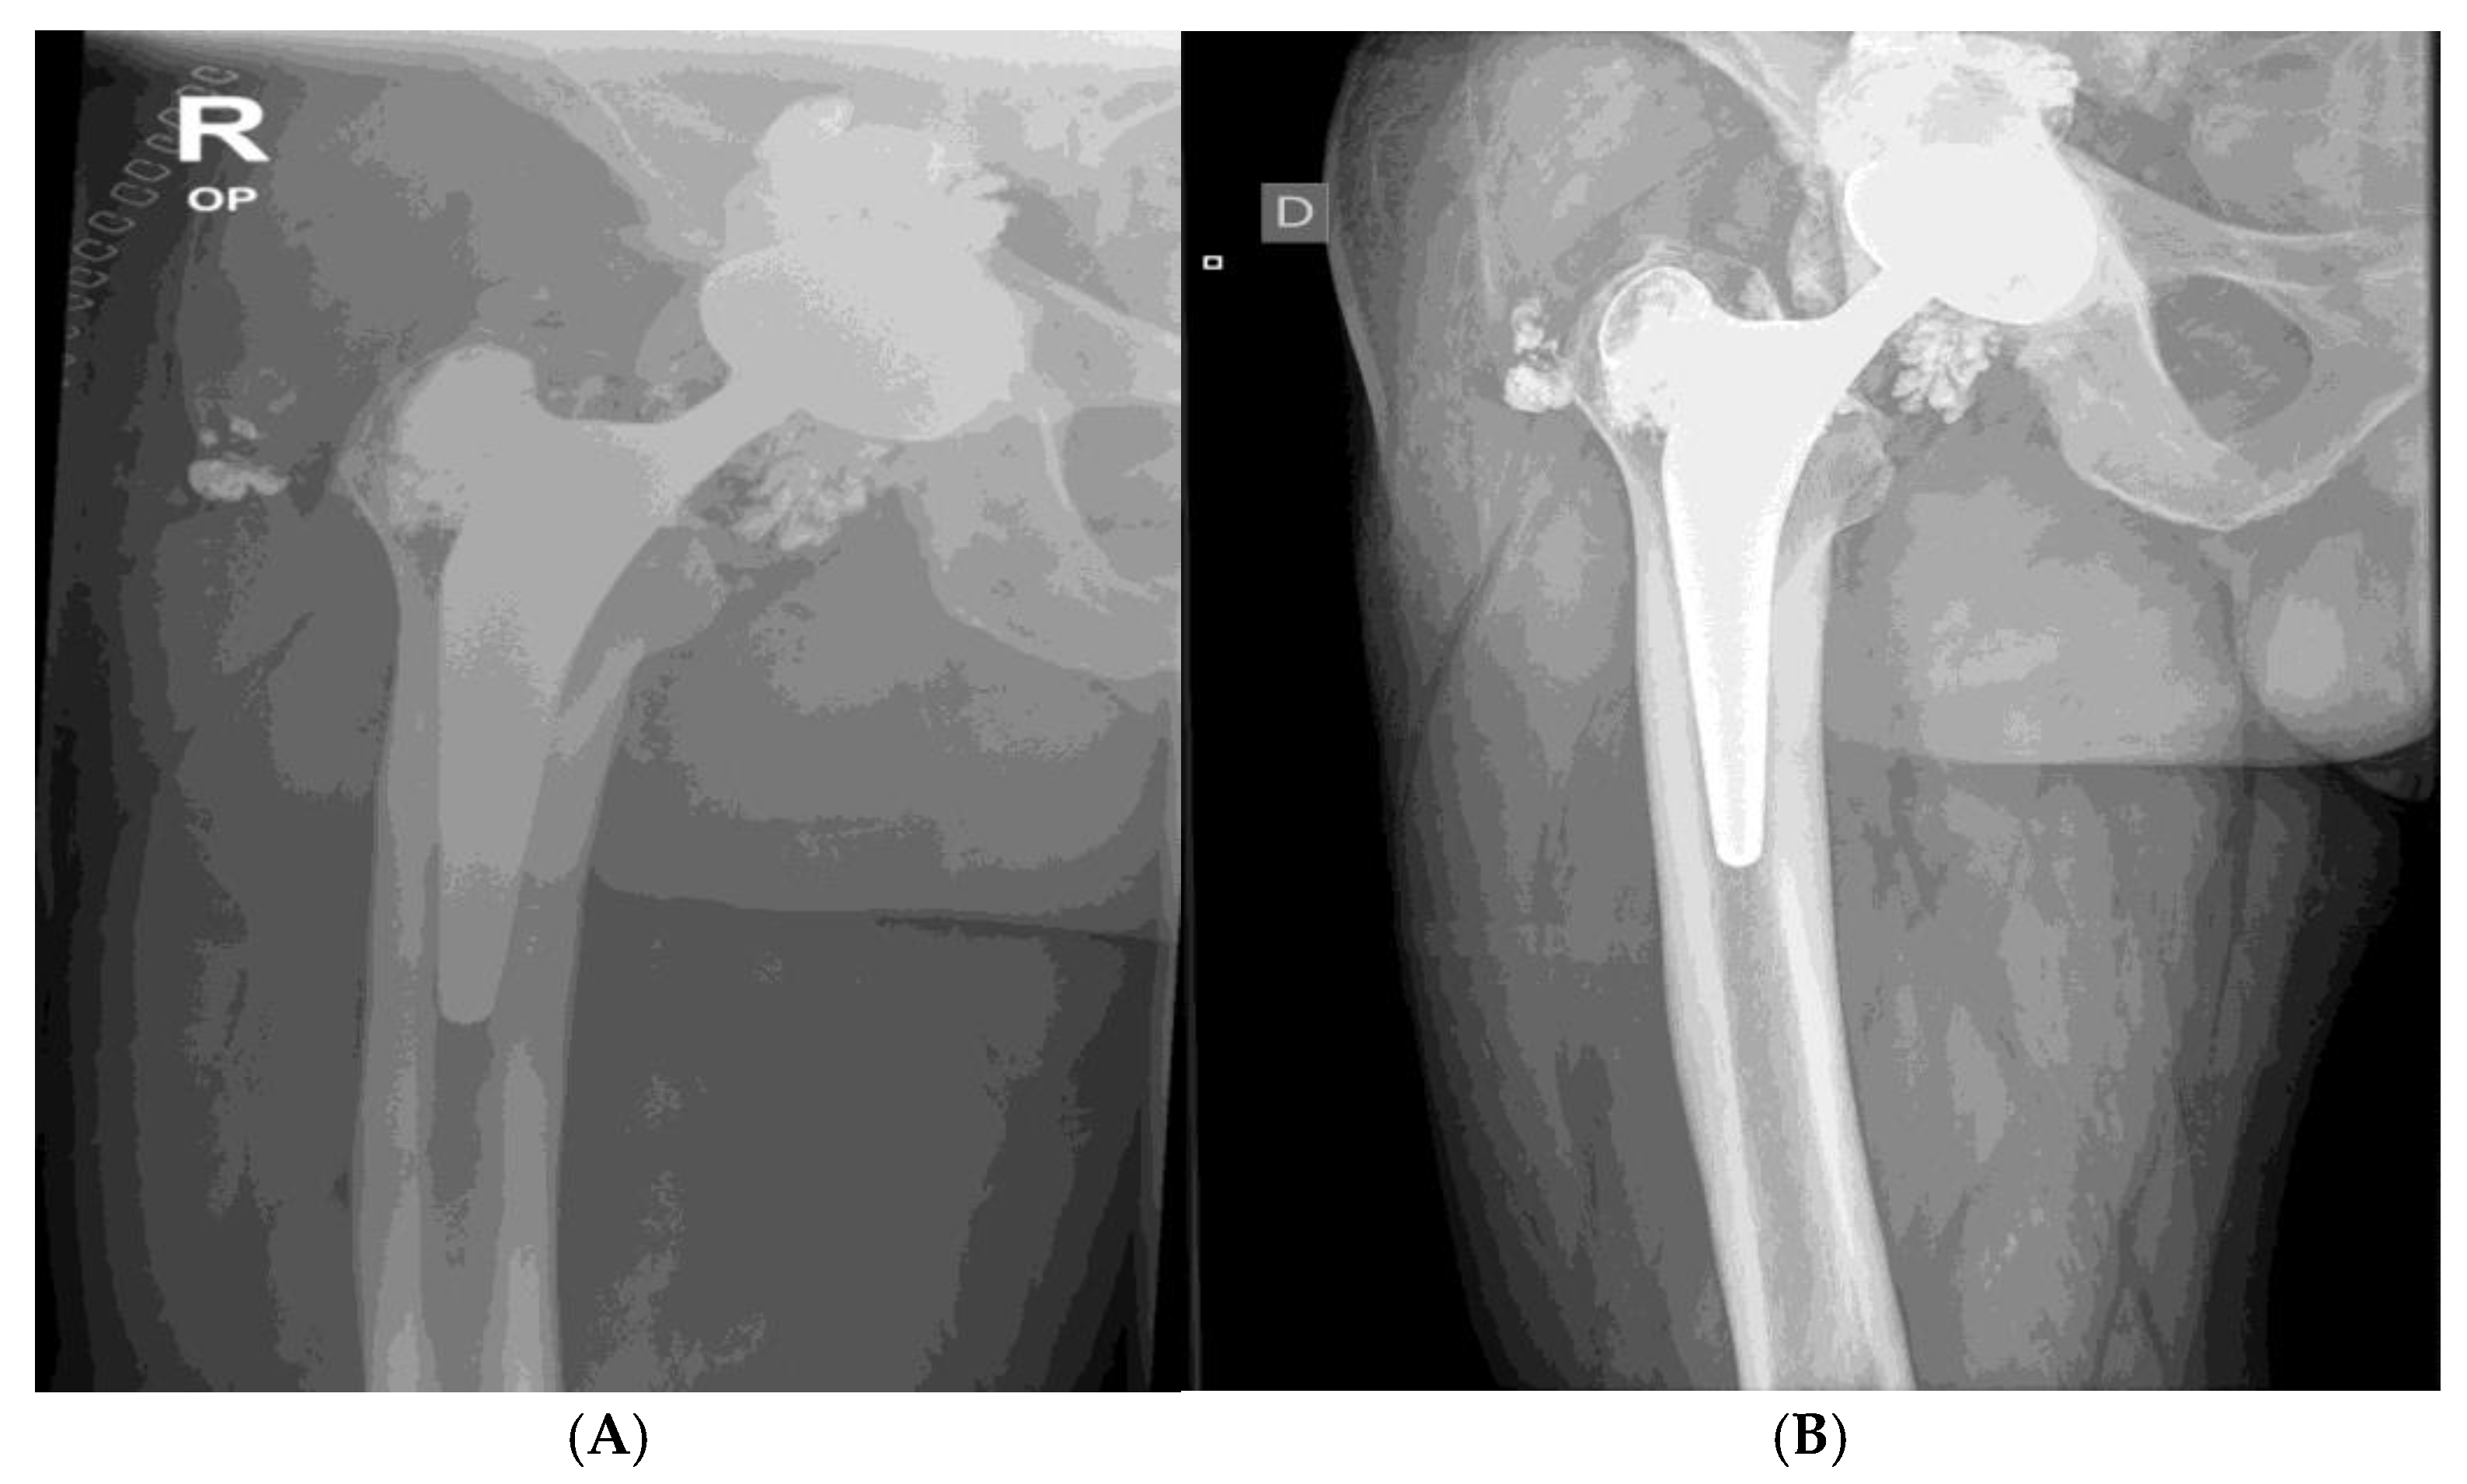

The initial radiographic evaluation showed no evidence of fracture or displacement of endoprosthesis components. However, in the weeks following the incident, the patient began reporting progressive worsening pain localized to the greater trochanteric region. Audible crepitus emerged shortly thereafter and became increasingly pronounced over time. 4 months after the fall, the patient presented for a follow-up evaluation, citing persistent and debilitating pain. Repeat radiographs demonstrated cranial migration of the femoral head within the acetabulum, consistent with advanced polyethylene inlay wear.

He was admitted to the hospital for revision surgery after total hip arthroplasty (THA) due to pain, limited range of motion, audible crepitus, and radiographic signs of acetabular polyethylene inlay wear, Figure 3.

Figure 4. X-ray shows aasymmetrical positioning of the femoral head in the acetabulum- suggesting damage and/or wear of components. Direct contact of oxinium femoral head and Ti6Al4V acetabular cup is the cause for extensive metallosis around the prosthesis – cloud like appearance around endoprosthesis. Wear of metallic components is suspected, since wear of polyethylene acetabulum liner would not be seen on x-ray, apart from asymmetric positioning of the head. Oxinium femoral head suffered severe wear, especially diffusion layer, or so called »ceramic layer«. Left hip/ prosthesis- symmetrical positioning of components and femoral head- normal x-ray.

In Figure 5the X-ray shows aasymmetrical positioning of the femoral head in the acetabulum- suggesting damage and/or wear of components. Direct contact of oxinium femoral head and Ti6Al4V acetabular cup is the cause for extensive metallosis around the prosthesis – cloud like appearance around prothesis. Wear of metallic components is suspected, since wear of plastic acetabulum liner would not be seen on x-ray, apart from asymmetric positioning of the head. Oxinium femoral head suffered severe wear especially diffusion layer, or so called »ceramic layer«